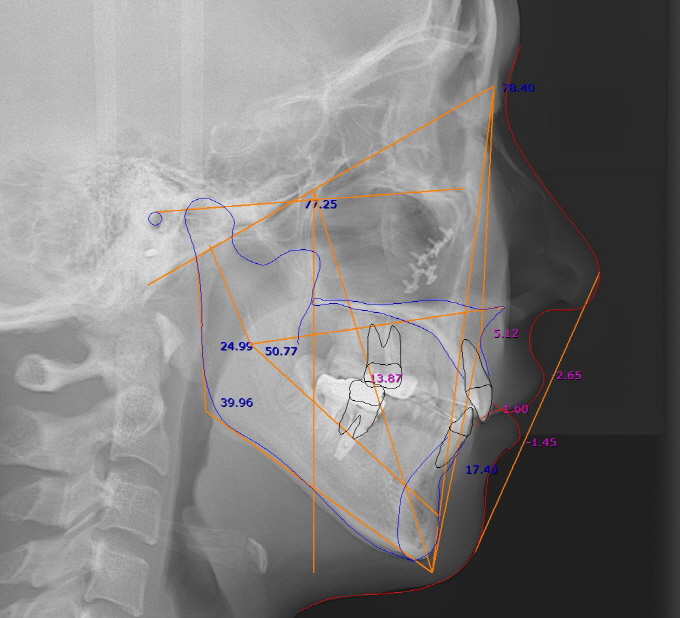

| Fig. 1: 56¼¼ ¿©ÀÚ, ¼øÂ÷Àû Ä¡ÁÖÄ¡·á¿Í ¼ö¼ú ±×¸®°í ±³Á¤Ä¡·á µî Àå±â°£ÀÇ Ä¡·á ³¡¿¡ ¾ÈÁ¤µÈ ±³ÇÕ¿¡ °í¸¥ Ä¡¾Æ¹è¿À» ´Þ¼ºÇÏ¿´°í ´ÙÀ½ ´Þ Áß¼ø°æ ÇÏ¾Ç ÀüÄ¡ºÎÀ§¿¡ ´ëÇÏ¿© BiotypeÀÇ °³¼± ¹× Ä¡±Ù Çǰ³¸¦ À§ÇÑ Mucogingival Plastic Surgery¸¦ ¿¹Á¤Çϰí ÀÖ´Ù. |